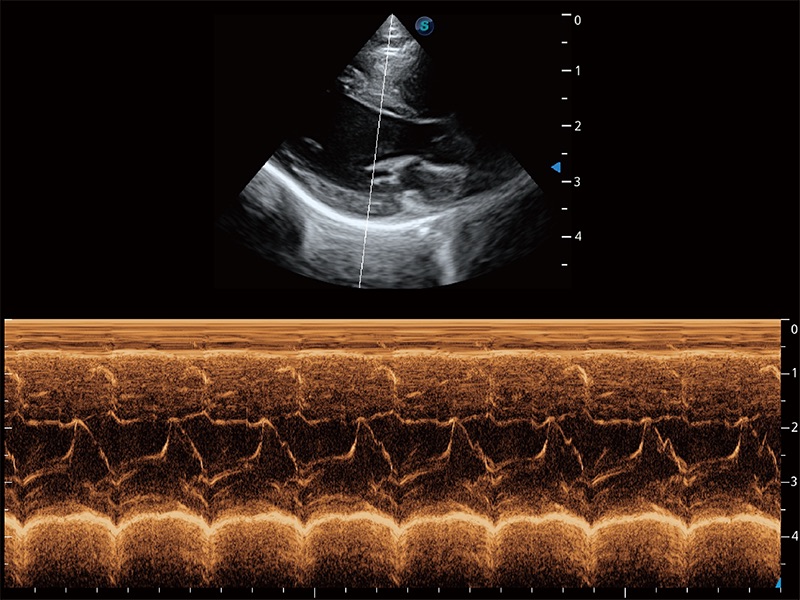

Ausgestattet mit dem gesamten Sortiment an Phased-Array-Schallköpfen von SonoScape (S1-5, 7P-A, 8P1), hochentwickelter Verarbeitungstechnologie und modernsten kardiologischen Tools bietet die ProPet-Serie Tierärzten eine umfassende ABklärung der Herz- und Myokardfunktionen.

Nutzt myokardiale Doppler-Frequenzverschiebungen zur Quantifizierung der myokardialen Gewebebewegung, wobei Rot und Blau die unterschiedlichen Bewegungsrichtungen der Herzwände darstellen. Durch die Kombination von TDI und PW lässt sich die Bewegungsbahn der Myokardwand besser erfassen.

Erfasst Daten mit bis zu 3 Messlinien auf einmal, um die Wandbewegung detailliert beurteilen zu können. Verbessert die Reproduzierbarkeit und Genauigkeit der linksventrikulären Messwerte erheblich.